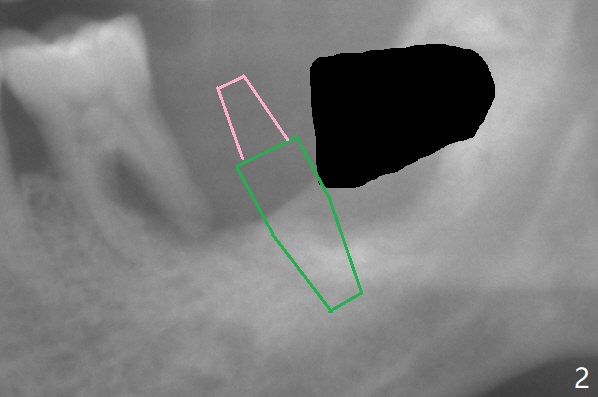

A 65-year-old man agrees to have an implant at #18 immediately after #17 extraction because of abutment screw loosening at #30. But the patient refuses #19 extraction. Since there is severe vertical bone loss at #18 (Fig.1), the implant should be as large as possible and tissue-level (Fig.2, 5 or 6x14 mm). The abutment is expected to be 5 mm long. After implant osteointegration, the abutment should be cemented with Panavia V5. To control infection at #19 temporarily, scale and place Arestin.